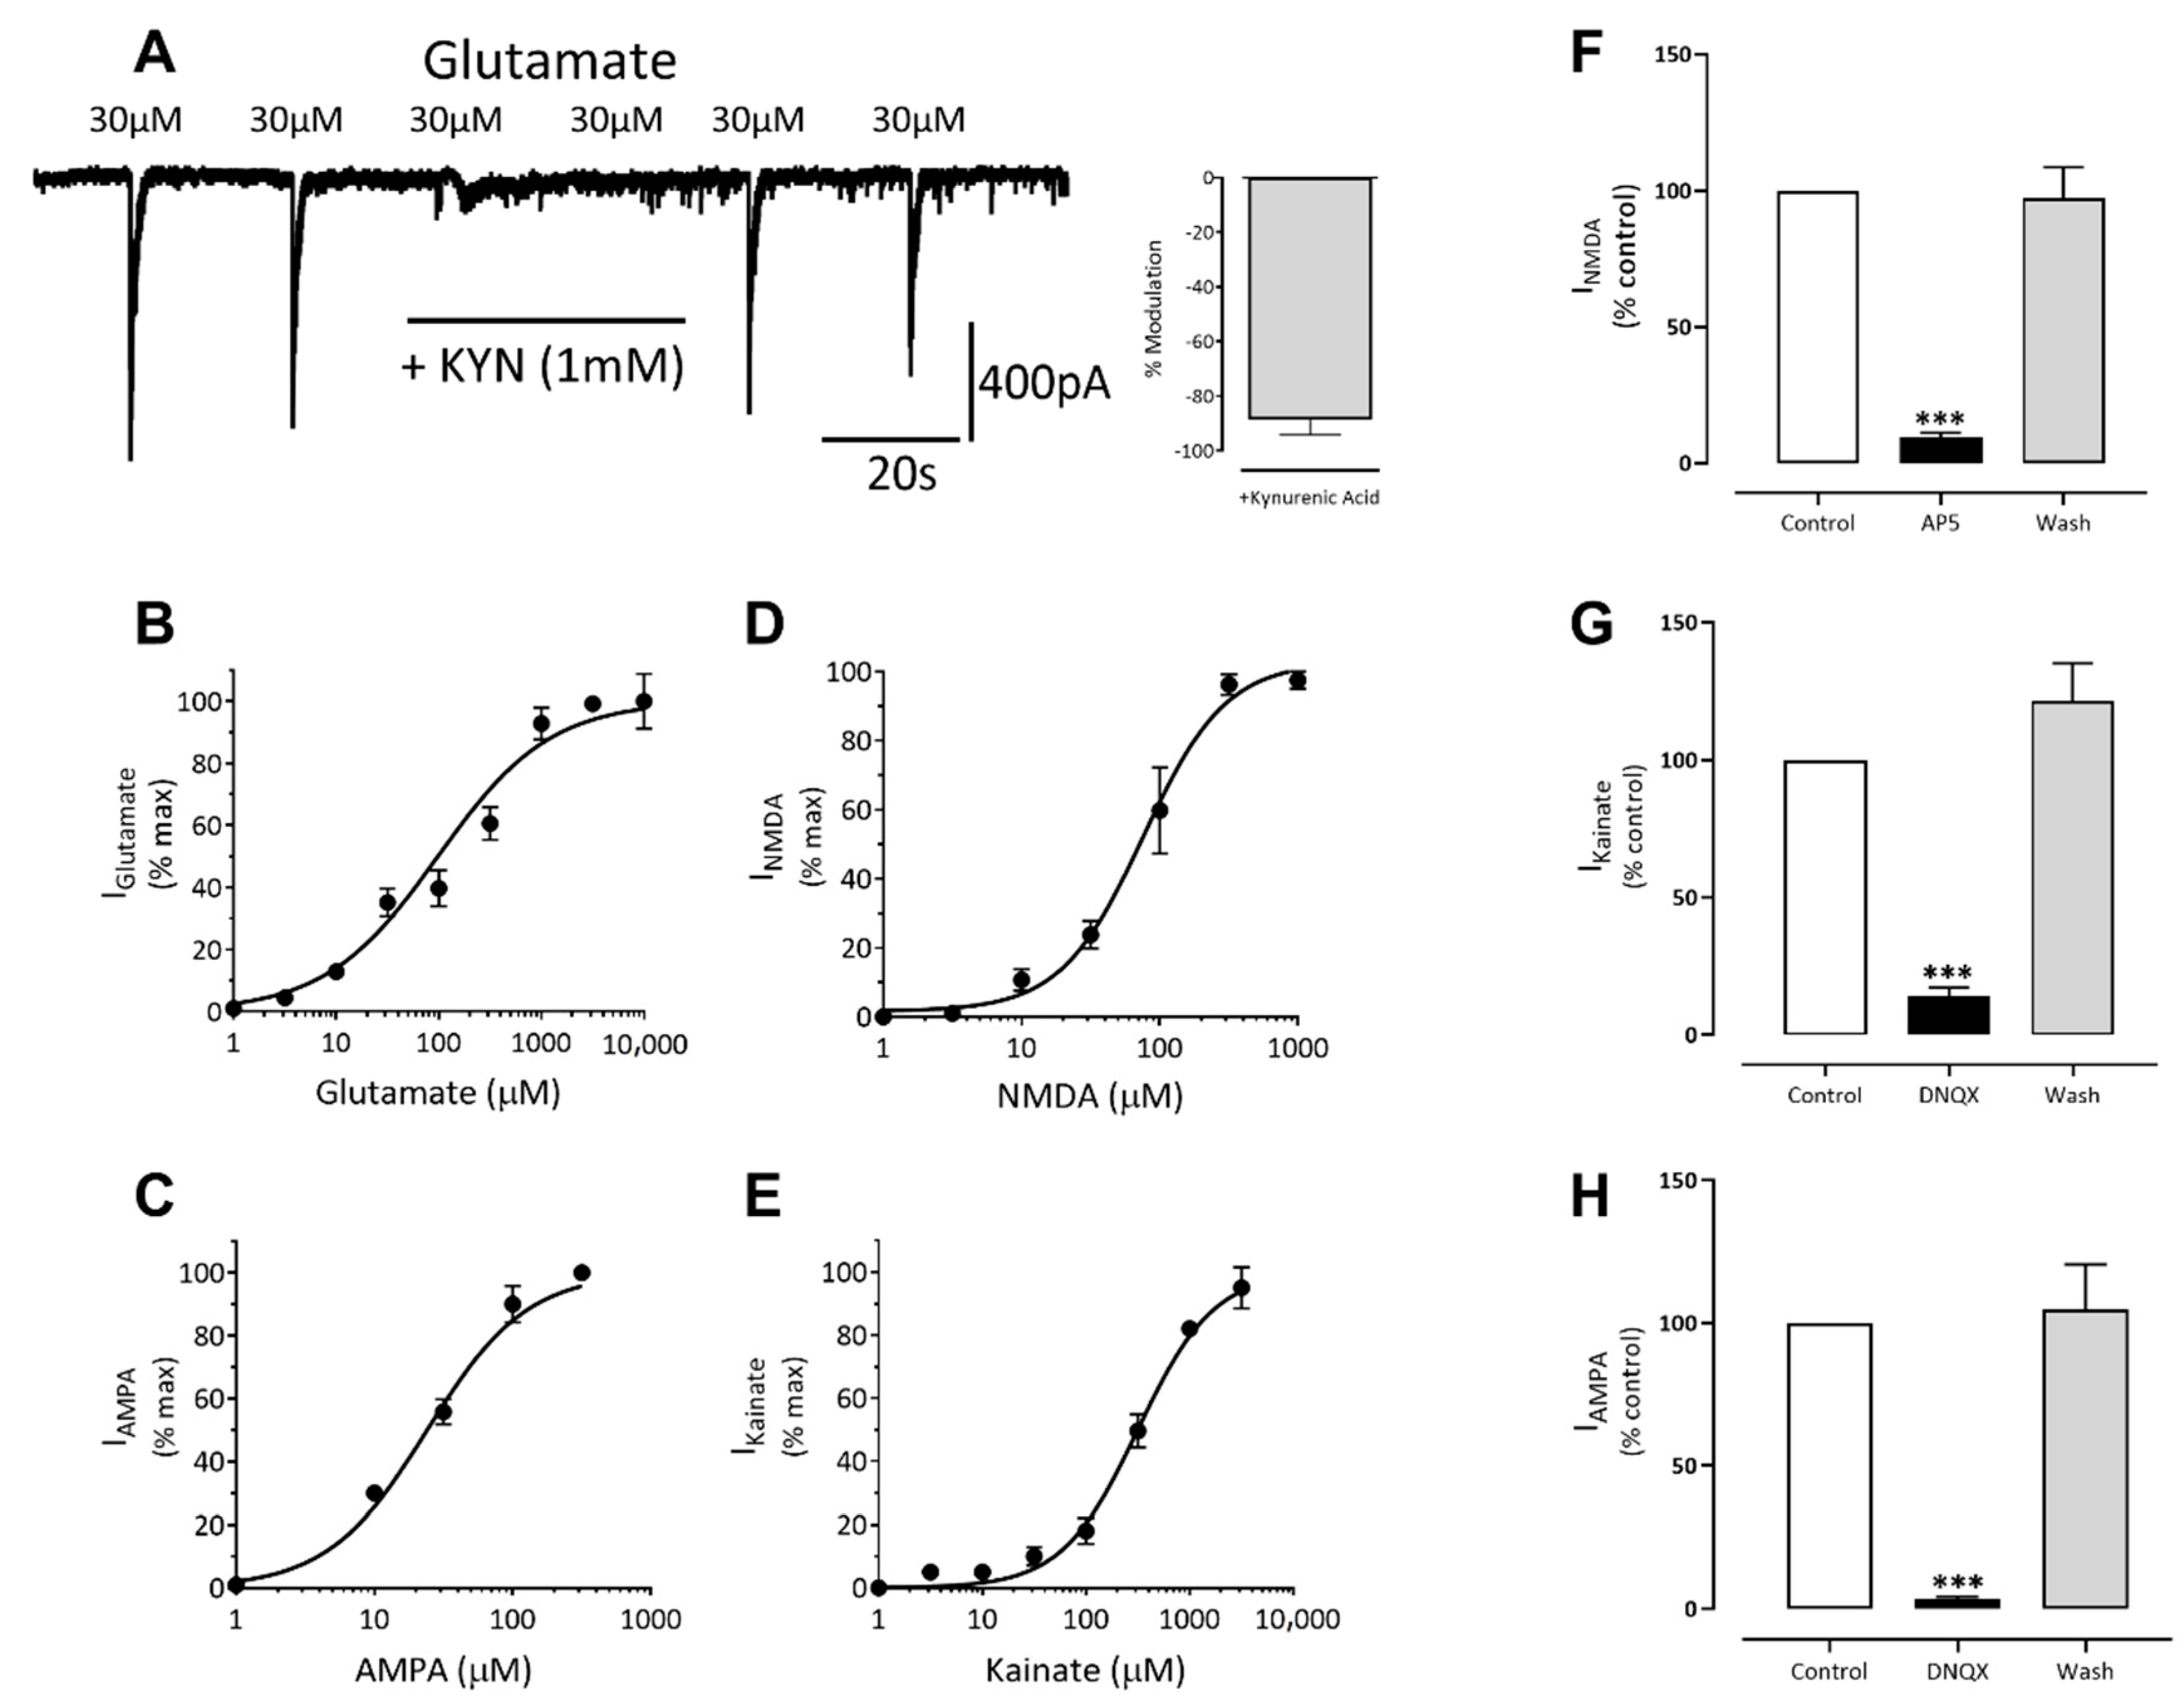

3.3. Excitatory Ligand-Gated Currents